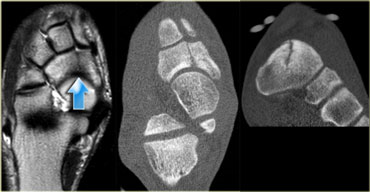

Stress fracture of sesamoid of great toe: sagittal STIR and axial CT. Stress fracture of sesamoid of great toe: sagittal STIR and axial CT.

On the left a 14-year old male soccer player with persistent plantar forefoot pain.

Stress fracture of the medial sesamoid of the great toe is indicated by a high signal intensity on an MR sagittal STIR-sequence at presentation.

A CT performed at presentation shows sclerosis of the medial sesamoid and confirms the diagnosis of stress fracture.